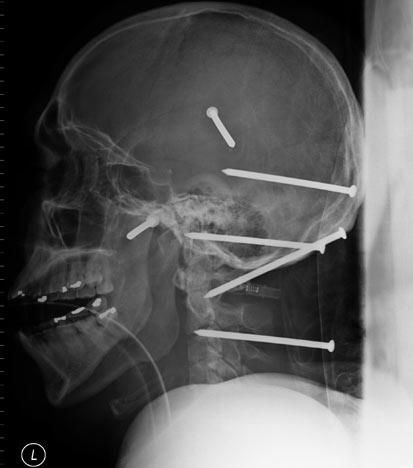

Radiografías de Israel Mahir, un trabajador de construcción, quien sobrevivió tras sufrir un accidente con un martillo eléctrico. Fue atendido en el Providence Holy Cross Hospital de Los Ángeles, California en 2004. Splash News